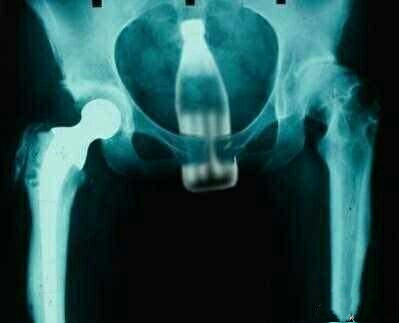

一件事是,一位大叔竟然用长达30cm的茄子准备疏通便秘,结果茄子竟然顶上心脏,差点危及生命,幸好该大叔在实在无法继续忍受疼痛后,找医院救治,方才化险为夷。

至于大叔当初到底真正是怎么想的,没有人知道,但是,另外一位男子,竟然用螺母套在*处私**玩耍,目的就一目了然了。

关键是螺母不但是铁,而且还是合金的,虽然这螺母也有个母字,可完全没有一点宽容的意思,而男子私物却是肉体凡胎,无法用扳手像下螺母一样给搬下,因此,男子*处私**充血,螺母无法取下,且螺母坚不可摧,医生也束手无策。

幸好还是消防官兵有办法,利用特别工具方将螺母弄破,男子*处私**才得以保全。